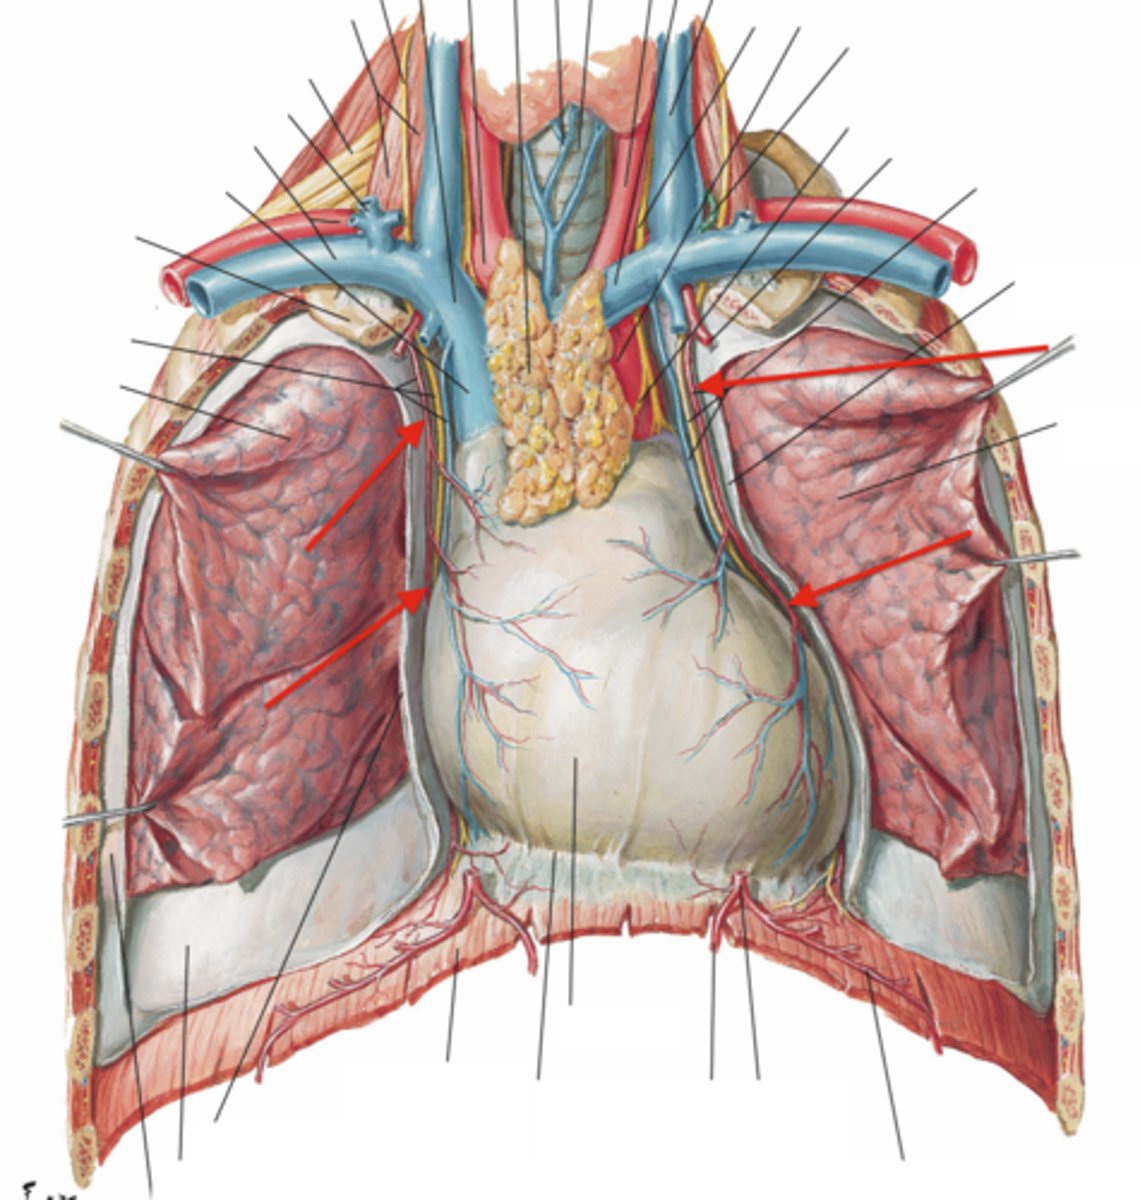

vagal trunks (left and right)

esophagus

descending aorta

phrenic nerves

pericardiophrenic arteries (and veins)